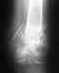

Добрый день прошу Вашей помощи!Моя мама 2 года назад сломала шейку бедра.Была сделаны 3 операции: 1. вставили два болта2. заменили один из отторгающихся болтов3. вынули после срастанияСначала была только хромота, потом стали усиливаться боли и хромота.Недавно сделали снимок - головка разрушается - нужна операция - вставление искусственного сустава за 1800 уе.Деньги есть. Но мама очень боится, говорит много случаев неудачных результатов. Посоветуйте пожалуйста хоть что-то. Могу представить дополнительную информацию